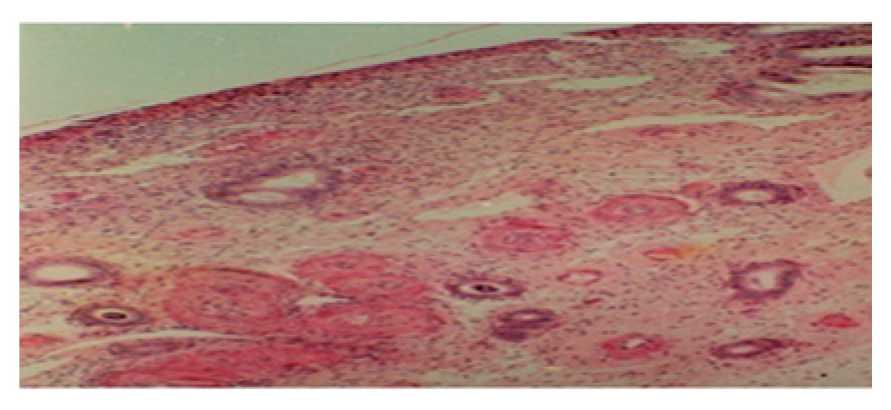

3.1. From 3rd Postpartum Day

3.2. Between 5th and the 7th Day Postpartum